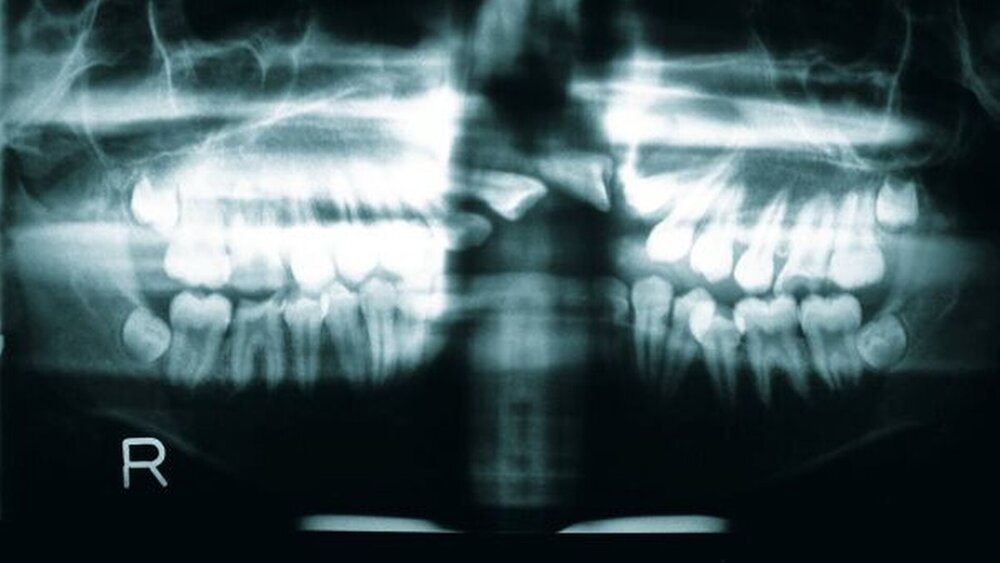

Die radiologische Untersuchung bestand aus einem Orthopantomogramm (OPTG), einer Aufbissaufnahme sowie einer Fernröntgenseitaufnahme (FRS). Neben der Übersicht der Gebissituation mit Nachweis des nicht durchgebrochenen Zahnes 22 im OPTG (Abbildung 3) war in der Aufbissaufnahme der Umfang der knöchernen Gaumenspalte klar zu erkennen (Abbildung 4). Das FRS ließ – bis auf die vertikal anterior verkürzte Maxilla und eine Protrusion der anterioren Prämaxilla – einen weitgehend normalen knöchernen Befund diagnostizieren (Abbildung 5).